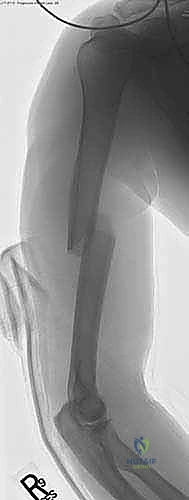

1. التخدير والوضعية (Anesthesia & Positioning):

يتم إعطاء المريض تخديراً عاماً، وأحياناً يُضاف إليه تخدير موضعي للأعصاب (Nerve Block) لضمان عدم الشعور بأي ألم بعد العملية لعدة ساعات. يوضع المريض في وضعية "كرسي الشاطئ" (Beach Chair Position) المائلة، أو وضعية الاستلقاء مع إمالة الذراع، مما يتيح للدكتور هطيف وصولاً حراً للكتف واستخدام جهاز الأشعة السينية التداخلية (C-arm) بسهولة.

2. الشق الجراحي الدقيق (The Incision):

يقوم الدكتور هطيف بعمل شق جراحي صغير (لا يتجاوز 3-5 سم) في الجزء الأمامي الجانبي للكتف. يتم فصل ألياف العضلة الدالية بلطف شديد بدلاً من قطعها، مع الانتباه التام لعدم تجاوز المسافة الآمنة لحماية العصب الإبطي.

3. تحديد نقطة الدخول (Entry Point):

هذه هي الخطوة الأكثر حرجاً في الجراحة. يجب إدخال المسمار من نقطة محددة جداً أعلى عظم العضد. يفضل الدكتور هطيف إدخال المسمار من منطقة "الحديبة الكبرى" (Greater Tuberosity) أو الحافة الغضروفية، لتجنب إتلاف الغضروف المفصلي للكتف (Rotator Cuff)، مما يمنع حدوث آلام الكتف المزمنة التي كانت شائعة في التقنيات القديمة.